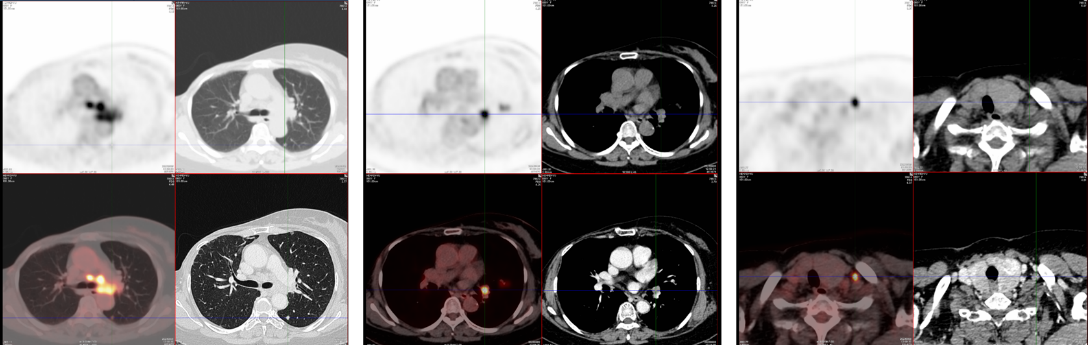

至2022年12月,患者CEA及CA15-3持续升高;2023年6月进一步检查提示疾病全面复发,DFS约60个月。PET/CT显示左肺上叶下舌段结节、区域多发肿大淋巴结以及胸腰椎多发骨质破坏,并伴糖代谢增高,提示肺、淋巴结及骨转移。

随后行超声支气管镜(EBUS)取材,转移灶仍表现为Luminal B1型,其中11L淋巴结ER 3+ 99%、PR 1+ 5%、HER2 2+且HER2基因无扩增、Ki-67约10%+;4R淋巴结ER 3+ 95%、PR 1+ 10%、HER2 1+且HER2基因无扩增、Ki-67约12%+。这提示患者虽已进入晚期阶段,但肿瘤仍保留较明确的激素受体驱动特征。

在一线阶段,患者于2023年6月接受哌柏西利联合氟维司群,并联合双膦酸盐类治疗。对于HR+/HER2-晚期乳腺癌而言,这一方案符合当下标准治疗思路。然而,至2024年6月复评时,患者出现纵隔淋巴结进展及骨转移进展,虽然肺部病灶达到PR,但总体仍判断为一线进展。这意味着患者并未获得与经典研究中相符的持久一线控制,也提示其肿瘤可能存在较强的早期耐药驱动。

治疗一周期后,影像学显示病灶明显缩小。在后续维持治疗中,靶病灶达到完全缓解(CR),非靶病灶状态为non-CR/non-PD。患者维持深度缓解状态,二线PFS高达17个月。